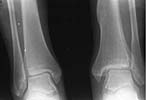

Comparative images of both ankles AP (Image 3) and Lateral view (Image 4) - in standing with loading are provided.

Now her complaints are pain and swelling around the ankle after loading and mediolateral instability because of deficiency of deltoid ligament and syndesmosis. No pain at rest. Ankle ROM is almost full.

It appears at the postop films that a small fragment was impacted to the joint medially, and displacement of Volkmann's triangle was increased a bit. Now we see early appearance of ankle arthritis. What should be done with the patient? It looks too early to fuse the joint. Ankle revision, modelling resection/arthroplasty? Ligament repair? Something else?